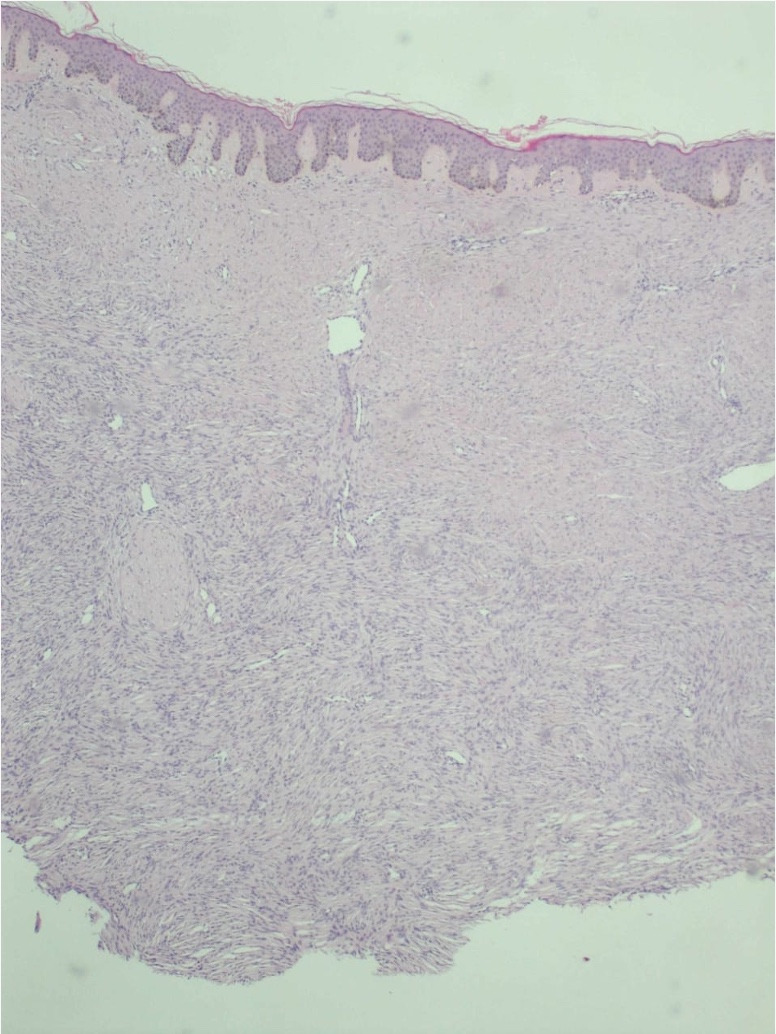

Objetives: Dermatofibrosarcoma protuberans is a sarcomatous neoplasm with low incidence. It exhibits slow growth; however, it has the capacity to involve deep tissues. Clinically, it can mimic benign lesions, presenting as thickened or atrophic plaques that slowly transform into protruding lesions. The treatment of choice is surgical excision, with Mohs micrographic surgery standing out for its advantages.

Clinical case: A 40-year-old male patient with dermatofibrosarcoma protuberans on the back underwent excision using the Mohs technique, with no tumor recurrence after two years of follow-up. Conclusion: It is important to highlight that the Mohs technique offers advantages over conventional methods, allowing for tissue optimization, ensuring clear margins, and achieving a low recurrence rate

Conclusion: It is important to highlight that the Mohs technique offers advantages over conventional methods, allowing for tissue optimization, ensuring clear margins, and achieving a low recurrence rate